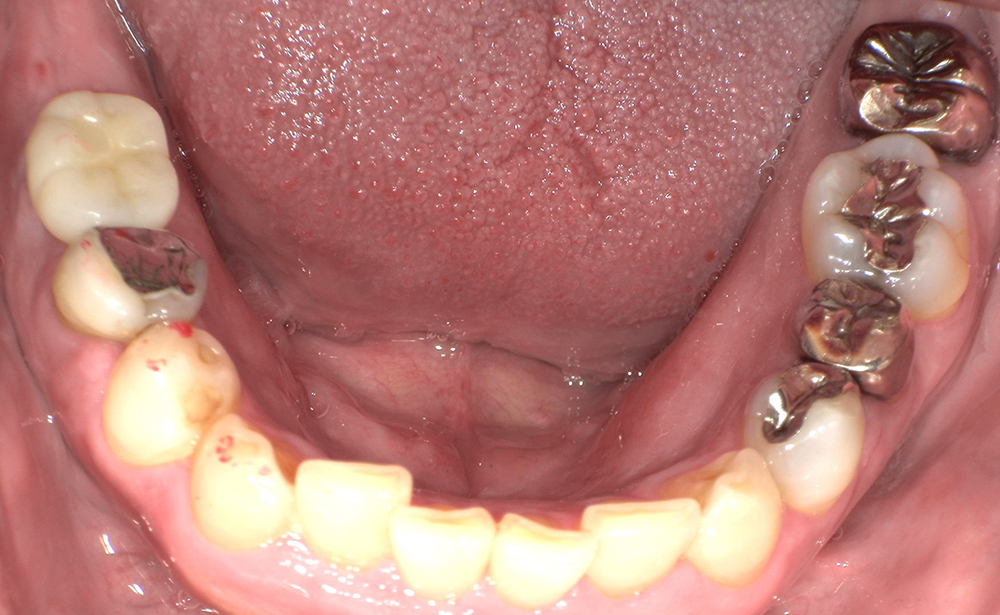

-

<治療前>

<治療後>

主訴:左下の奥歯が折れた。

処置内容:抜歯即時 ストローマンインプラント2本埋入

費用:¥880,000(税込)

治療期間:2カ月

副作用・リスク:

一時的に腫脹が出ますが1週間程度で消失します。